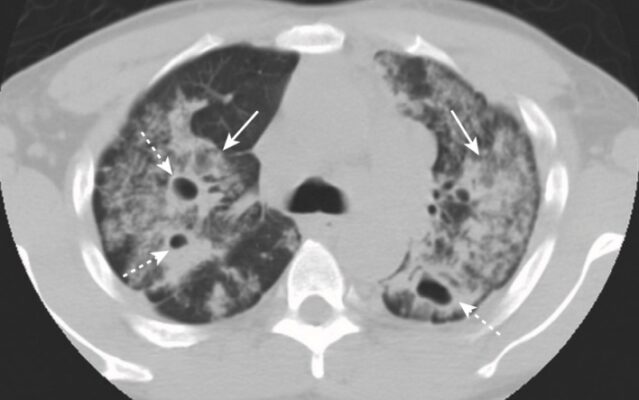

- Vi sinh vật nguyên mẫu gây ra viêm phổi hang là vi khuẩn lao (Mycobacterium tuberculosis).

- Tạo hang thường gặp trong lao hậu tiên phát (lao tái hoạt) nhưng hiếm gặp ở lao nguyên phát. Các hang thường nằm ở các thùy trên, hai bên và có thành mỏng, bờ trong nhẵn và không chứa mức dịch – khí (Hình 7). Sự lây lan xuyên phế quản (từ một thùy trên sang thùy dưới bên đối diện hoặc đến một thùy khác trong phổi) sẽ khiến bạn nghĩ đến nhiễm khuẩn Mycobacterium tuberculosis.